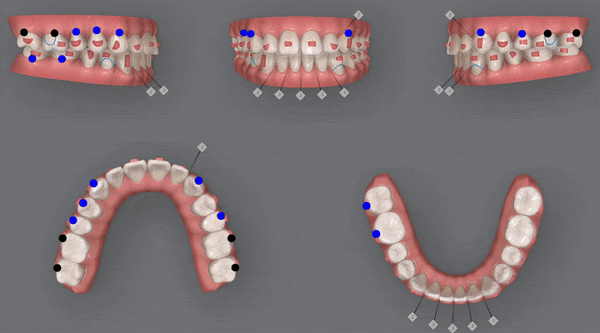

4th(11개)

네번쩨 클린체크를 끝으로

정말 디테일한 부분까지 상호보완, 개선하여

좀더 섬세한 작업을 통해 마무리를 해드렸습니다 ^^

전체적으로 위,아랫니들이

제 위치를 찾으며 정리가 되었습니다!!

어금니들의 대이동이 끝이나고

클린체크의 예상대로 교정 마무리가 잘 되었어요!!

윗니와 아랫니 사이의 틈이 사라지고,

윗니를 덮고 있던 아랫니들이 제 위치를 찾으며 부정교합이 개선되었을 뿐만 아니라

정중앙선이 일치하도록 마무리 해드렸습니다 :)